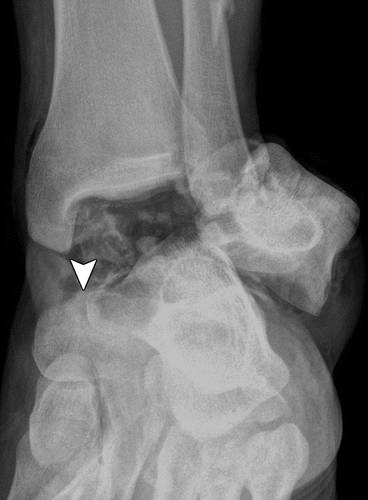

这种损伤必须与三角骨 - 一个附件后骨小梁区分开来。 在放射照相术中,后过程的断裂显示不规则的边缘(图13),而三角骨是圆形或椭圆形,具有光滑的皮质边缘(图14)。 双侧X线照片的价值有限,因为据报道三分之二的病例是双侧的(32)。 如果射线照片不确定,应进行CT。

图14 三角骨。 踝部的侧面X线片显示在距骨后方的椭圆形皮质骨化(箭头)。